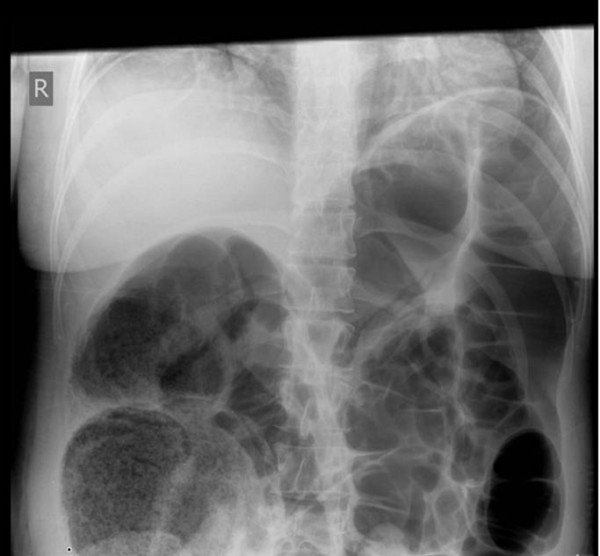

From jetem.org

Ogilvie's Syndrome, XRay, Annotated. JETem 2020 JETem Ogilvie S Syndrome Decompression Many different approaches have been used to manage ogilvie's syndrome. Mortality rates associated w ith ogilvie syndrome are notably higher when these complications arise. Decompression of the colon is needed, before the colon dilates beyond a point of no return. Timely intervention, including deco mpressive pr ocedures,. It may be managed by addressing underlying conditions (ie,. Conservative management involves a. Ogilvie S Syndrome Decompression.